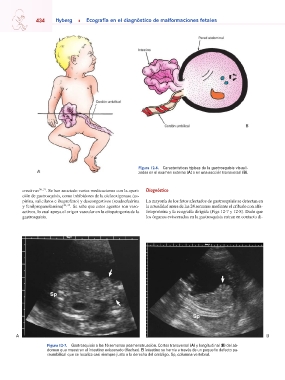

Figura 12-7. Gastrosquisis a las 16 semanas posmenstruación. Cortes transversal (A) y longitudinal (B) del ab-

domen que muestran el intestino eviscerado (flechas). El intestino se hernia a través de un pequeño defecto pa-

raumbilical que se localiza casi siempre justo a la derecha del ombligo. Sp, columna vertebral.